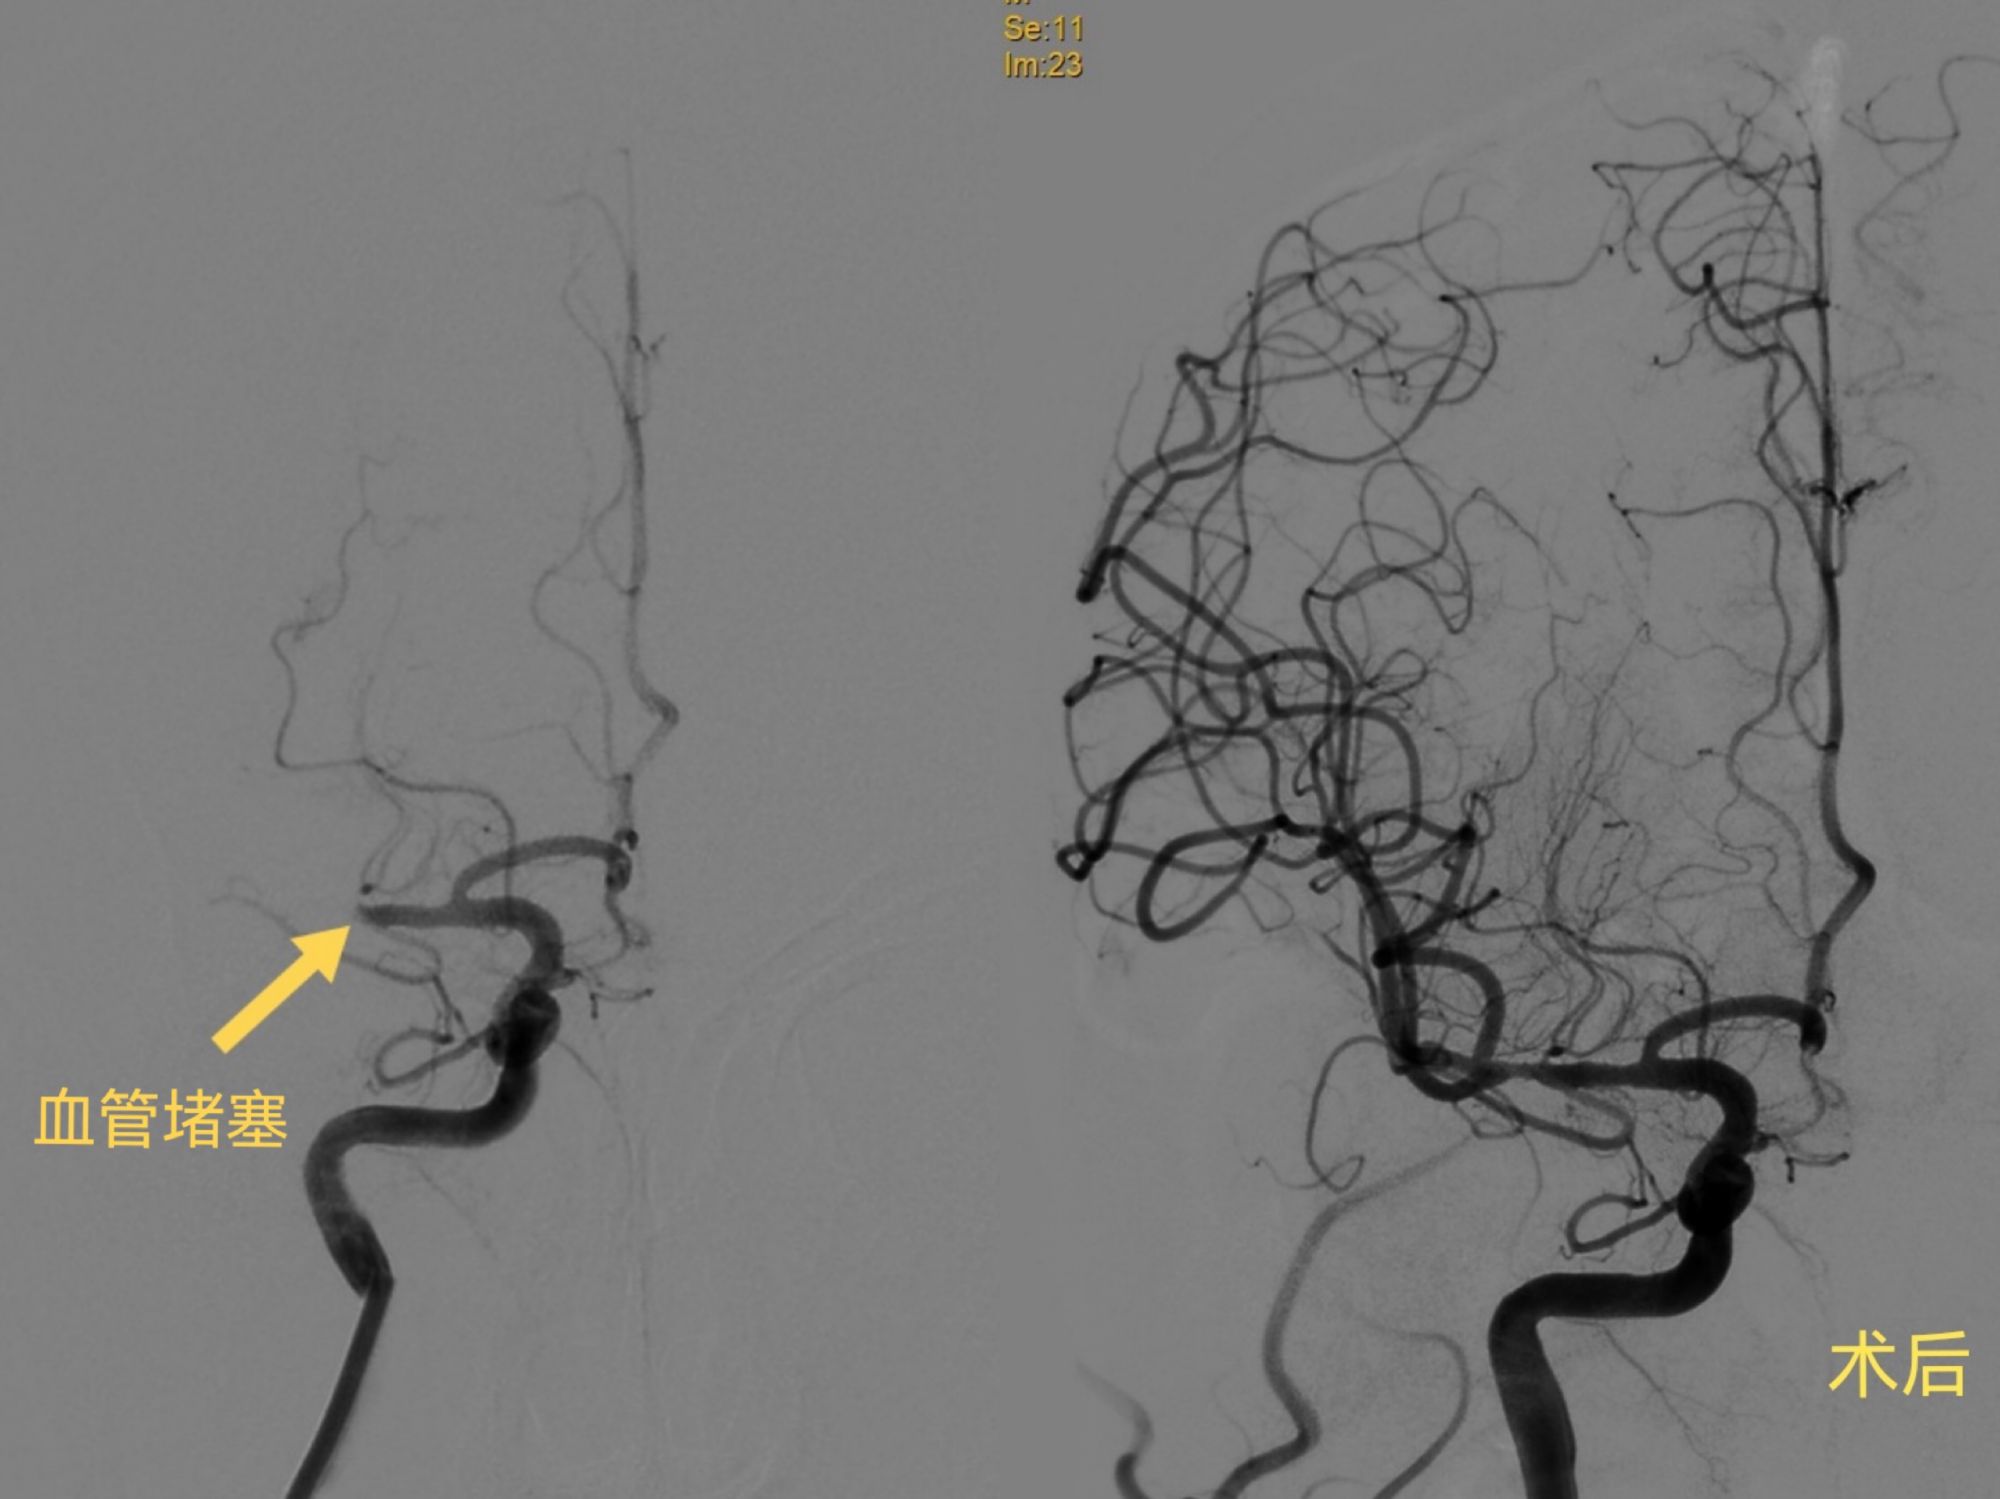

严峻的新冠疫情打破了人们的正常生活,桓台县人民医院卒中中心的医护人员,积极参与疫情防控工作的同时,调整卒中救治流程,提高脑卒中患者的救治效率,近期为4例急性脑梗死患者进行取栓治疗,均成功开通血管。 “ 3月19日,刘先生突然出现意识不清、左侧肢体瘫痪,病情危重。急诊科立即为病人开通了绿色通道,完成CT检查的同时进行了核酸快速检测。卒中小组会诊后考虑患者心脏栓子脱落,导致脑栓塞,建议急诊取栓手术。脑血管介入团队医生在做好防护的同时,争分夺秒为患者进行造影、取栓,从动脉穿刺到开通血管,仅用时33分钟。 脑卒中是一种发病率高、致残率高、死亡率高和复发率高的常见疾病,静脉溶栓和动脉取栓是急性脑卒中的重要治疗手段,可显著降低患者的死亡率和致残率。 怎样预防脑卒中的发生: 控制高血压是预防中风的重点,高血压患者应根据医生的建议按时服用抗高血压药物,最好每天测量一次血压。 保持情绪稳定,并注意气象因素的影响,季节性和气候变化会使高血压患者情绪不稳定。 日常生活饮食应注意以清淡为主,可以多吃些新鲜的水果及绿色蔬菜,忌食辛辣刺激和过度油腻生冷的食物。忌烟酒、熬夜等对人体伤害或者透支的习惯。 桓台县人民医院卒中中心友情提示:疫情当前,请大家遵守疫情防控要求,适当进行室内运动,规律作息。如果突然出现言语不清、口角歪斜、肢体麻木无力,高度怀疑是脑卒中,务必第一时间就医。